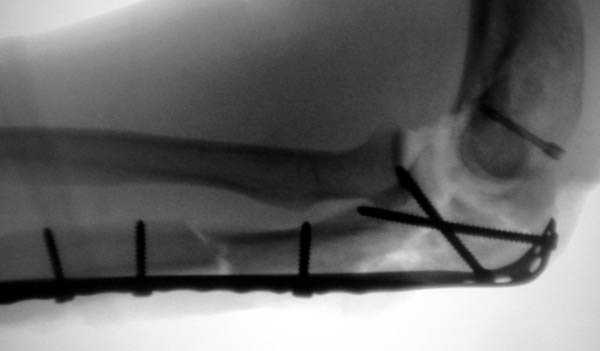

Предложенные реконструктивные пластины в 3.5 мм

идеальны для фиксации при отрывном или флексионном

переломе, когда имеется большой фрагмент.

Здесь выставлены несколько случаев и варианты фиксации локтевого отростка, некоторые в комбинации с другими переломами.